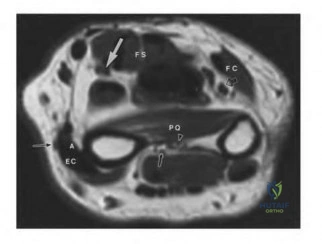

A 25-year-old patient suffers a severe crush injury to the hand. Clinical evaluation raises suspicion for compartment syndrome of the hand. How many distinct fascial compartments are recognized in the hand that may require release during fasciotomy?